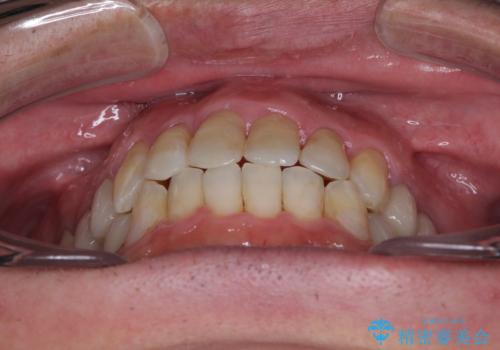

飛び出した前歯と目立つ銀歯 矯正とセラミックの総合歯科診療

ワイヤー矯正を併用したことで、上顎前歯はあっという間に整いました。

補綴治療にあたり、痛みのある歯に対して根管治療を行うこととしましたが、処置が必要な歯が多かったため、期間を要しました。

補綴治療中に前歯のデコボコが戻ってしまったため、補綴治療後にインビザラインを1セット追加して仕上げました。